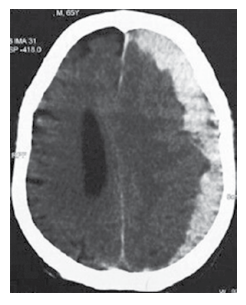

Homem de 72 anos chega ao pronto-socorro com náuseas, vômitos e cefaleia nas últimas 36 horas. O familiar relata quadro de irritação e esquecimento nas últimas duas 2 semanas. Ele leva um estilo de vida ativo, mas sofreu um acidente de bicicleta há 2 semanas. O histórico é notável para angina estável e hipertensão arterial. Ele bebe há 30 anos, quase que diariamente (cerca de 2 copos de uísque). Ao exame físico: ele está desorientado para o tempo, lugar ou pessoa; pressão arterial: 170 x 100 mmHg; reflexos tendinosos profundos: 4+/4 em hemicorpo esquerdo e 2+/4 à direita; Babinski positivo à esquerda. A tomografia sem contraste é mostrada a seguir

Considerando a principal hipótese diagnóstica, a conduta inicial correta é